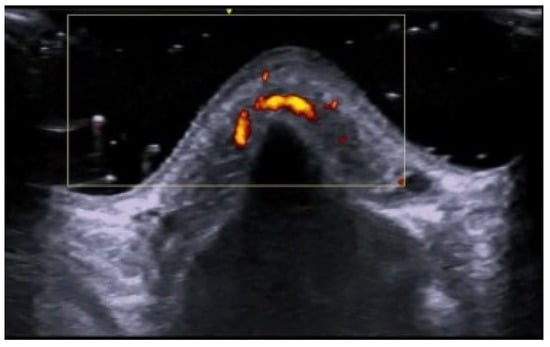

- Di Battista, M.; Vitali, S.; Barsotti, S.; Granieri, G.; Aringhieri, G.; Morganti, R.; Dini, V.; Della Rossa, A.; Romanelli, M.; Neri, E.; et al. Ultra-high frequency ultrasound for digital arteries: Improving the characterization of vasculopathy in systemic sclerosis. Semin. Arthritis Rheum. 2022, 57, 152105. [Google Scholar] [CrossRef] [PubMed]